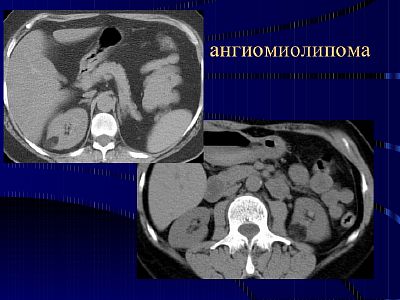

Ангиомиолипома почки представляет собой доброкачественную опухоль, состоящую из жировой ткани, гладкомышечных клеток и кровеносных сосудов. Врачи отмечают, что данное образование чаще всего встречается у женщин в возрасте от 40 до 60 лет и может быть связано с наследственными заболеваниями, такими как синдром Туберозного склероза. Многие пациенты не испытывают симптомов и обнаруживают опухоль случайно при проведении ультразвукового исследования или компьютерной томографии. Однако в некоторых случаях ангиомиолипома может вызывать боли в пояснице, кровотечения или увеличение почки. Врачи подчеркивают важность регулярного мониторинга таких образований, так как они могут расти и, в редких случаях, трансформироваться в злокачественные опухоли. Лечение может варьироваться от наблюдения до хирургического вмешательства в зависимости от размера и симптоматики опухоли.

В основном новообразования обнаруживаются на УЗИ или томографии. Заболевание распространено преимущественно среди женщин (старше 45 лет). У мужчин данный недуг встречается гораздо реже.